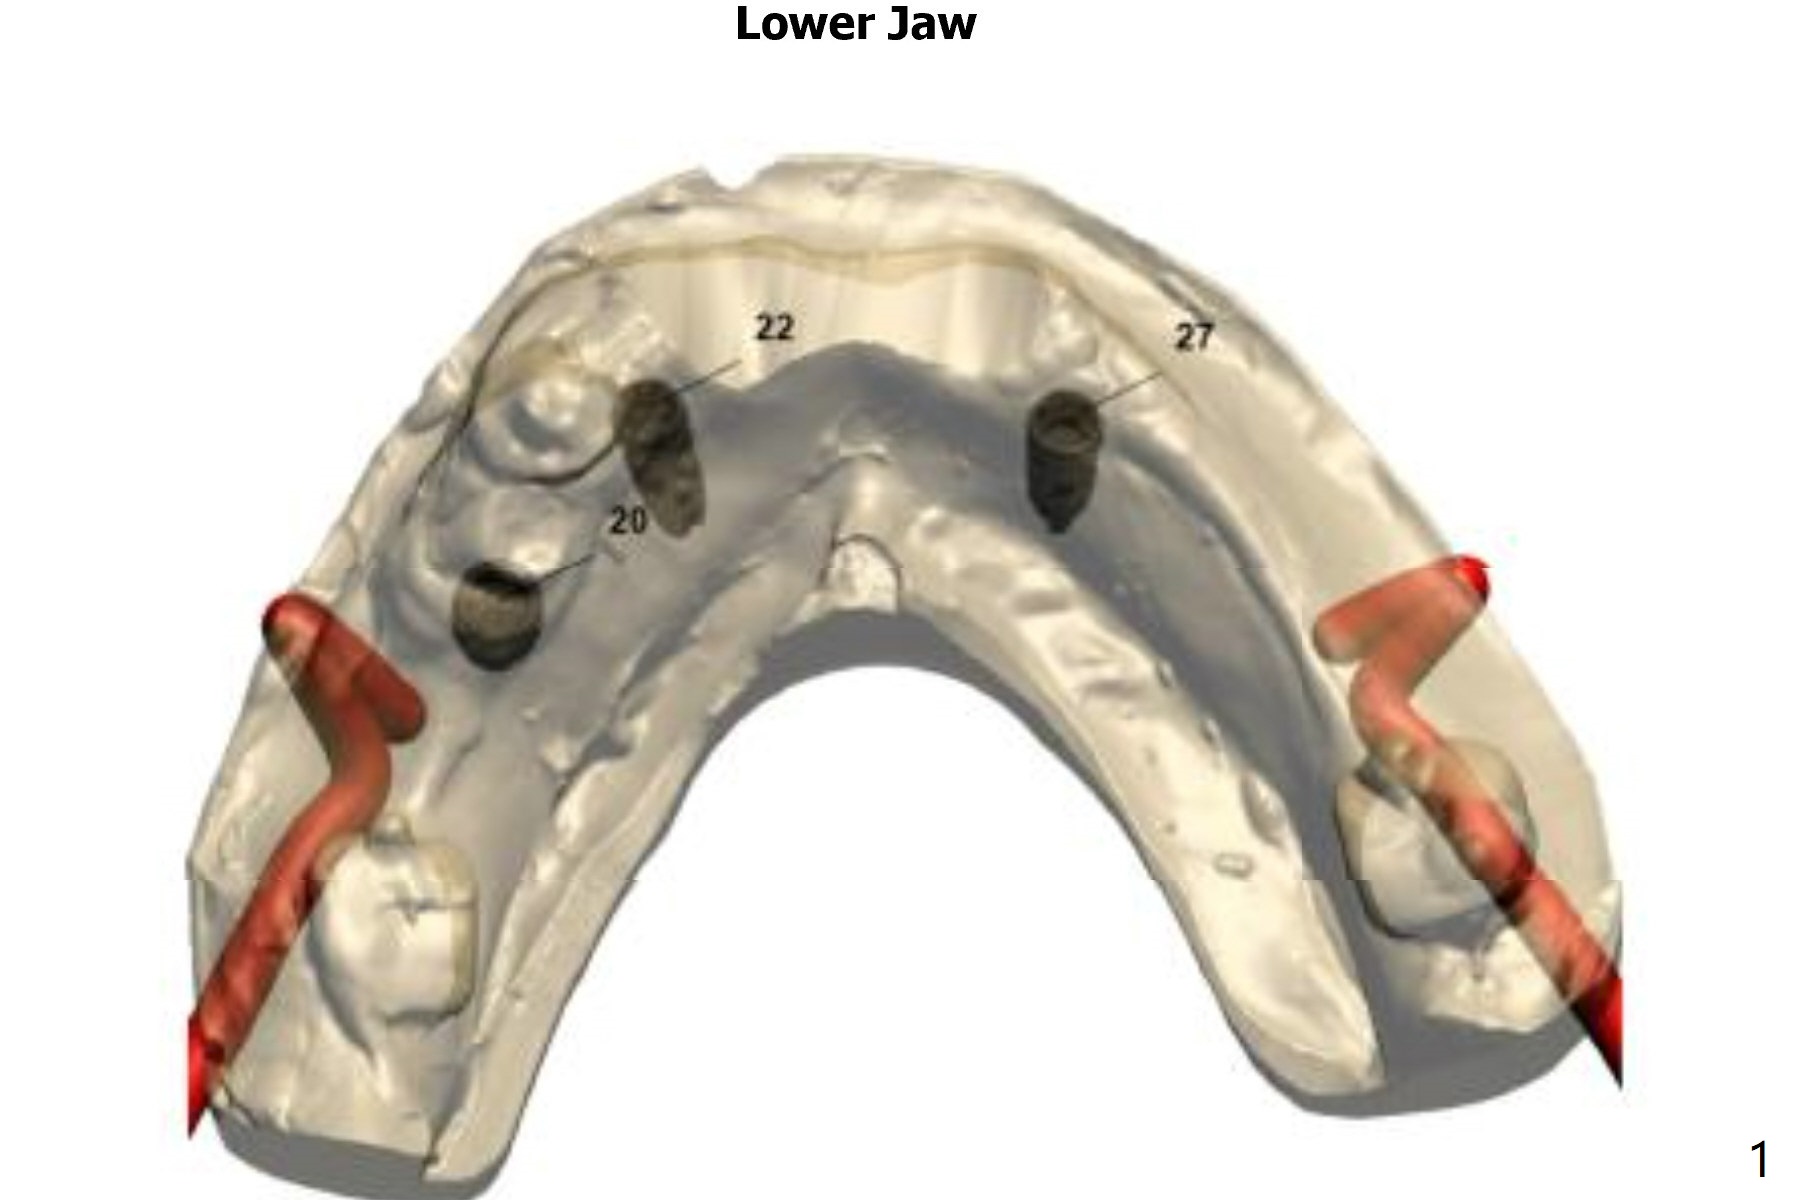

For placement of implants at #20, 22 and 27.

Immediate Implant,